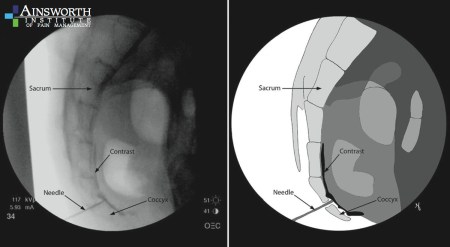

Ganglion impar block

As described, the procedure will require me lie face down on my stomach “with a pillow under the pelvis to help flatten out the lower lumbar spine’s natural curvature. Your lower back and intergluteal cleft [that’s ‘butt crack’ in layman’s terms] will be prepped and draped in a sterile manner before local anesthesia is administered at the point of entry of the needle into your skin. When your skin is adequately anesthetized, the needle will be advanced under fluoroscopy guidance until correct needle placement is obtained. Its correct placement will also be confirmed by administration of contrast dye. Once position is confirmed either a diagnostic block (to determine if your perineal pain is visceral or somatic), or a therapeutic block will be preformed.”